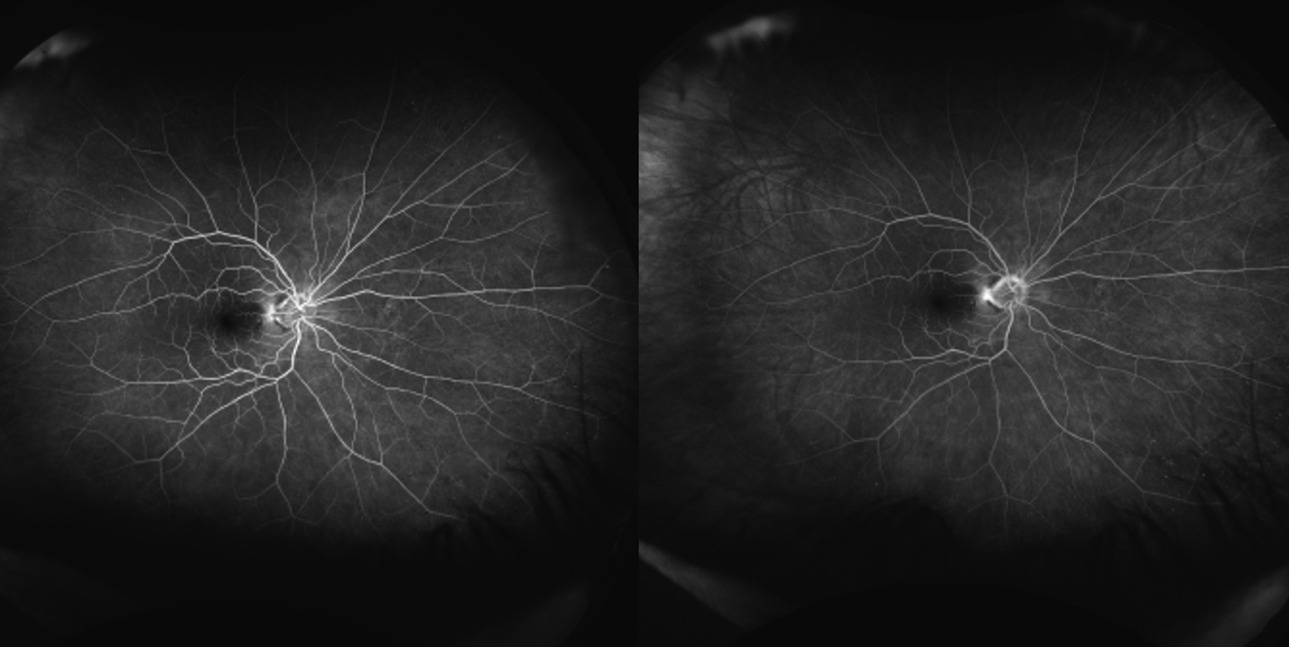

Spectralis optical coherence tomography of the macula demonstrated no evidence of macular edema in either eye. However, a line scan through the cotton wool spots showed focal thickening of the retinal nerve fiber layer (Fig. 3). Optos fluorescein angiography was normal and demonstrated no evidence of non-perfusion or leakage within posterior pole and peripheral retina (Fig. 4 & 5).